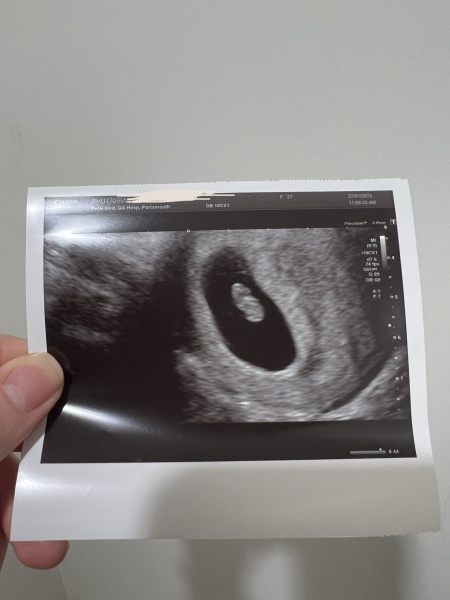

Hi all, I had an early scan at 5 weeks 6 days according to LMP and all they could see was gestational and yolk sac. I went back last Friday two weeks later and they saw my little bean with a heartbeat measuring 7+3 🥹❤️ just some reassurance for those that had the same outcome on an early scan! X

Congratulations! This is really reassuring as I had a scan at epu today after admission to hospital for ectopic and just saw sac and yolk sac at 5+2 and I have another scan for Friday 10th where I'll be nearly 7 weeks!